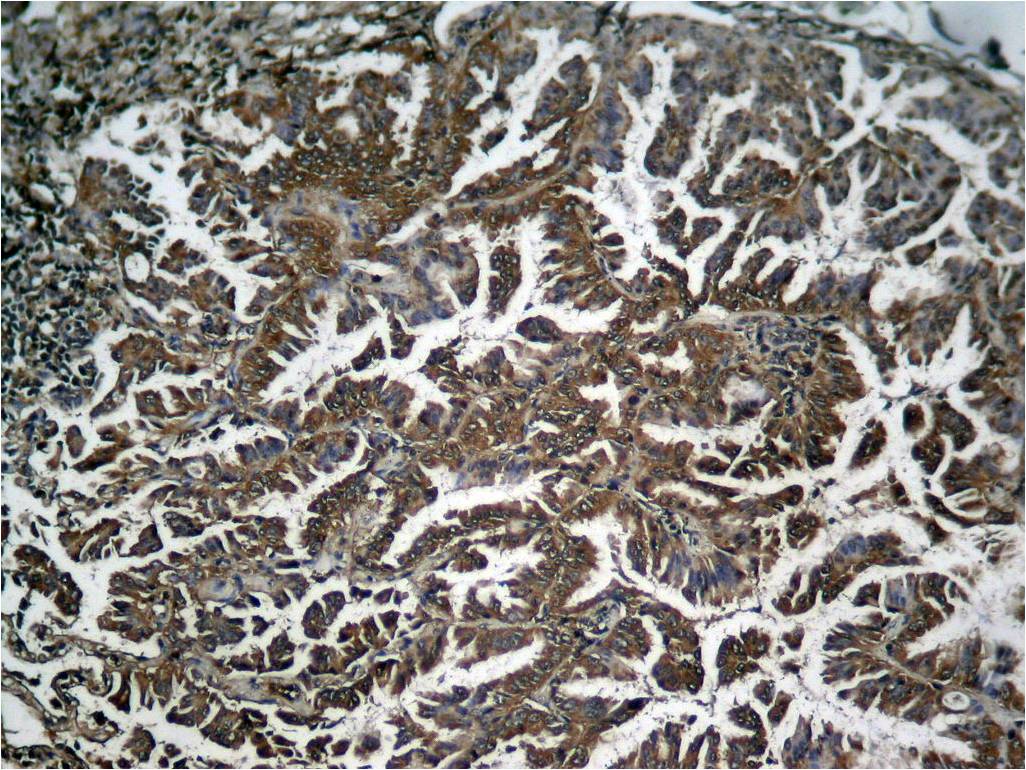

Immunohistochemical analysis of paraffin-embedded human Lung carcinoma tissue using NFκB-p65 (Phospho-Ser536) Antibody P40014.